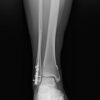

One of the largest MRI-based studies comparing knee injuries between men and women reveals surprising differences in injury patterns based on gender and age. The findings can be used to improve risk assessment and develop early intervention strategies. The study included 13,549 consecutive routine knee MRI exams performed between 2019 and 2024 at...